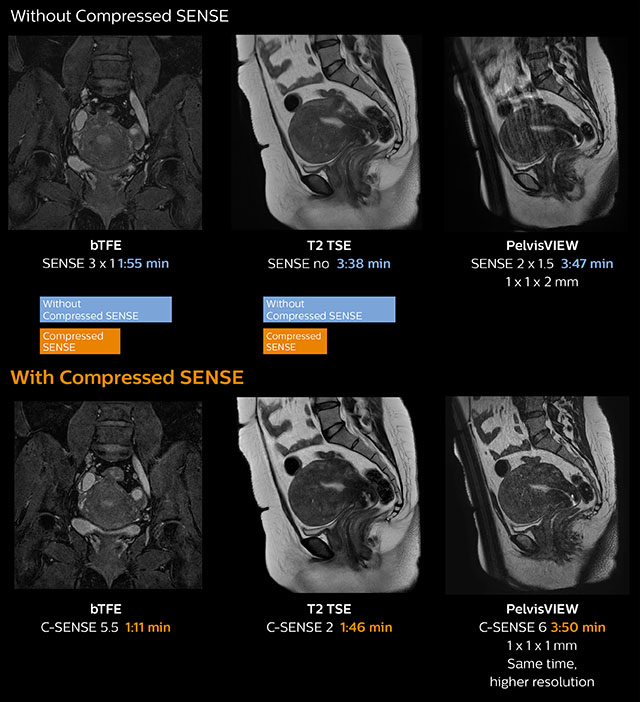

Pelvis with myoma – comparison w/wo Compressed SENSE

In this MRI exam of pelvis in a patient with myoma, Compressed SENSE is used to accelerate individual sequences and thus the entire examination on Ingenia 1.5T. Compressed SENSE allowed for a decrease in scan time for the T2 TSE from 3:38 to 1:46 minutes. The Compressed SENSE images in this case show fewer motion artifacts than the images from the previous protocol with SENSE. In 3D PelvisVIEW, the Compressed SENSE images have a higher and isotropic spatial resolution with a scan time similar to the SENSE sequence. The improved spatial resolution and better contrast in the myometrium of the uterus allowed radiologist Dr. Koyama to confidently diagnose the cancerous lesion in the uterus. The use of Compressed SENSE accelerates scanning times and increases spatial resolution in 3D PelvisVIEW.